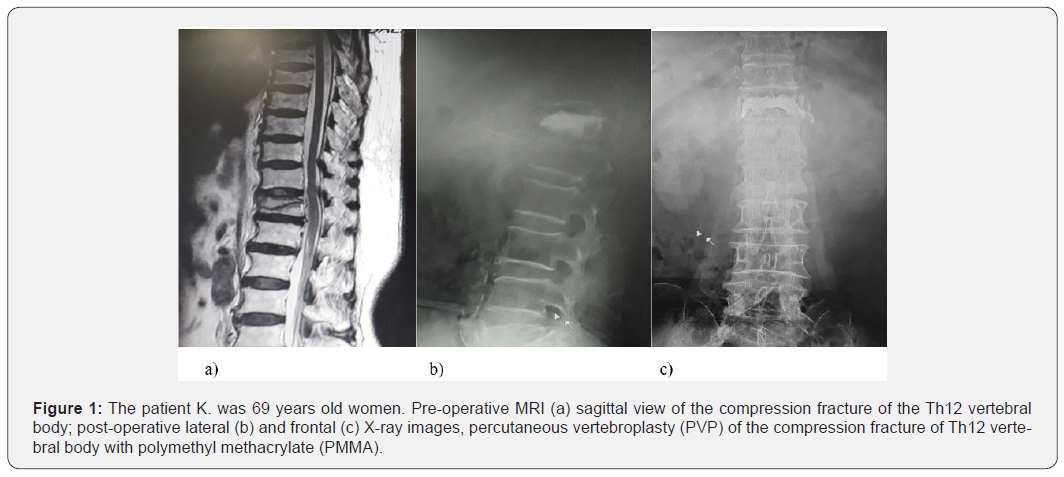

Another potential challenge is to define the optimal treatment algorithm in case of a cement encroachment into the spinal canal, which can lead to the spinal canal compression post PVP/ PKP. Currently, the operative treatment modalities succeeding failed PVP /KPP can be ranged from minimally invasive reaugmentation of the collapsed vertebra to the open or minimal invasive anterior/posterior instrumentations of the spine, or a combination of those surgical procedures. In the present case (Figure 1), the PVP was performed for the treatment compression vertebral fractures of the body Th12, however 3 weeks after the initial surgery, it was noted that bone cement encroachment into the spinal canal. The second surgery was open long-segment posterior fixation LSPF (2 levels above and 2 levels below of the fractured vertebra); this surgical modality provides enough stabilization without incurring the risks of posttraumatic kyphosis, implant breakage, and late neurologic deficit (Figure 2). The determination of the level of instrumentation of the spinal fractures is widely discussed in the literature to date, there are many studies compared the biomechanical and clinical outcomes of SSPF /LSPF constructs without fixation of the fracture level [7]. The results showed that SSPF/LSPF have the same radiographic outcomes (local kyphosis, sagittal index, anterior body height compression) [8]. The difference between SSPF and LSPF is that SSPF significantly declines the surgical time and preserves more vertebral motion segments, however the implant failure is less in the LSPF fixation than that of SSPF fixation [9]. It should be stressed that four-segment pedicle fixation is the most suitable option for osteoporotic patients, according to fundamental biomechanical principles, this structural uniform provides the greatest mechanical stiffness for initial fixation and can reduce the likelihood of segmental collapse [10].